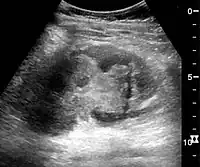

Complex cysts can have membranes dividing the fluid-filled center with internal echoes, calcifications or irregular thickened walls. The complex cyst can be further evaluated with Doppler US, and for Bosniak classification and follow-up of complex cysts, either contrast-enhanced ultrasound (CEUS) or contrast CT is used (Figure 6). The Bosniak classification is divided into four groups going from I, corresponding to a simple cyst, to IV, corresponding to a cyst with solid parts and an 85–100% risk of malignancy.[1] In polycystic kidney disease, multiple cysts of varying size in close contact with each other are seen filling virtually the entire renal region. In advanced stages of this disease, the kidneys are enlarged with a lack of corticomedullary differentiation (Figure 7).[1]

Figure 7. Advanced polycystic kidney disease with multiple cysts.[1]